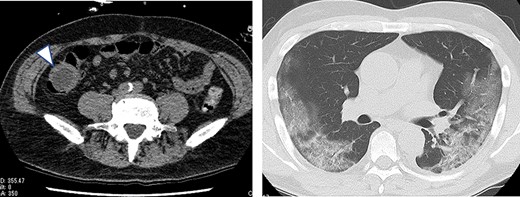

A 63-year-old male who had fever and dyspnea visited a medical institution. Both antigen and polymerase chain reaction (PCR) tests for SARS-CoV-2 were positive and he was hospitalized for treatment. Nine days after admission, he was transferred to our hospital due to deteriorating respiratory condition. After admission to our hospital, ventilator management and steroid administration were performed. After 3 days, his respiratory condition improved and he was able to withdraw from the ventilator. Computed tomography (CT) taken for observation of lung disease coincidentally showed cystic lesions in the right abdomen (Fig. 1). He had no abdominal symptoms at this time. The patient was discharged on the 18th day of hospitalization. He had diarrhea from the 15th day after discharge and abdominal pain from the next day. He consulted his family doctor on the 17th day because the abdominal pain persisted. CT examination revealed enlargement of cystic lesion and intussusception of the right colon (Fig. 2). The patient was transferred to our hospital as an emergency case. Physical findings showed fever with a body temperature of 38°C and tenderness in the right lower abdomen. Blood test showed an inflammatory reaction with a white blood cell count of 13 000/μl and C-reactive protein of 2 mg/dl. The SARS-CoV-2 PCR testing was negative. We performed emergency surgery on the same day.

Plain CT on the 13th day after COVID-19 onset (the day after withdrawal from the ventilator); a cystic lesion was found in the right lower abdomen (arrowhead).